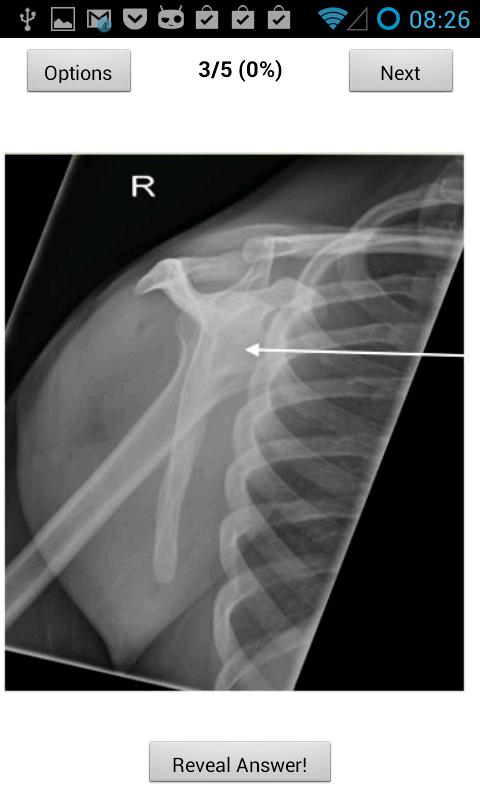

該應用程序有助於進行FRCR第1部分解剖學考試的放射學候選者。它包含60個免費考試式問題,每個問題都有一個標籤(按2013年的問題),可以選擇240個問題***在有限的時間內僅£0.50 *** ***